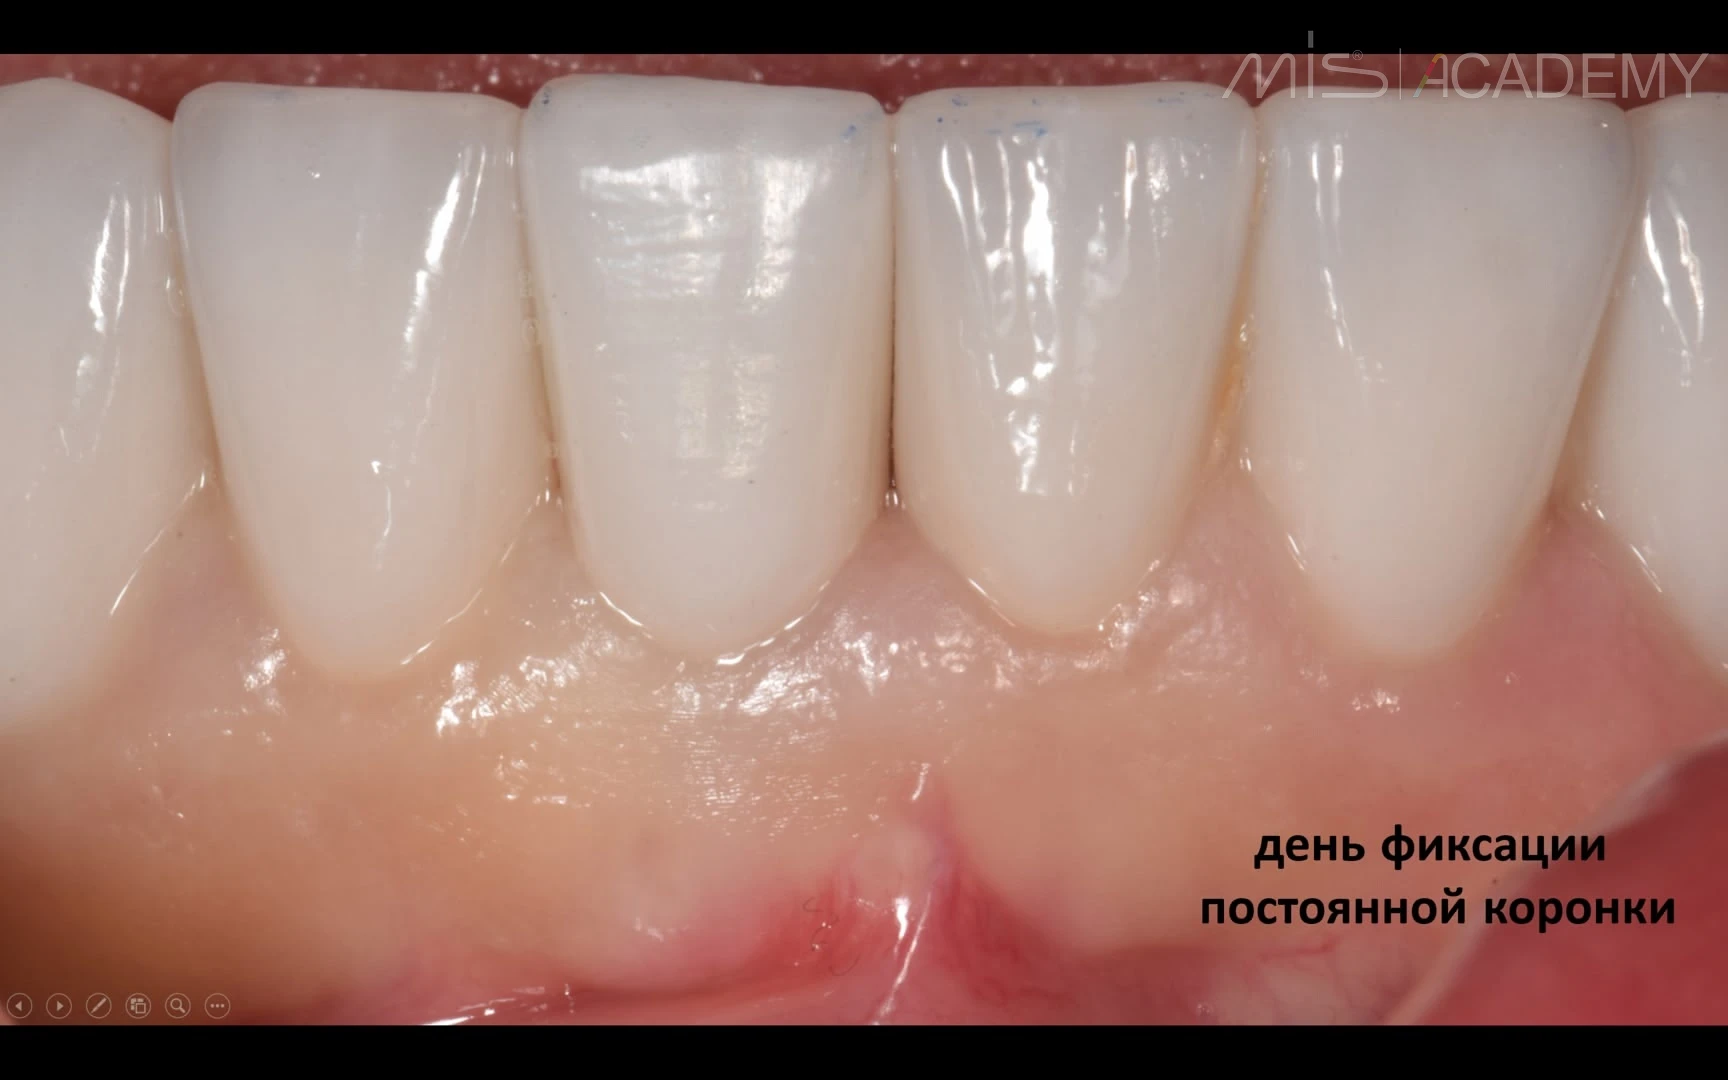

Результат через 5 месяцев — полное восстановление язычной стенки альвеолярного отростка. Замена временной коронки на постоянную циркониевую с полированной поддесневой частью.